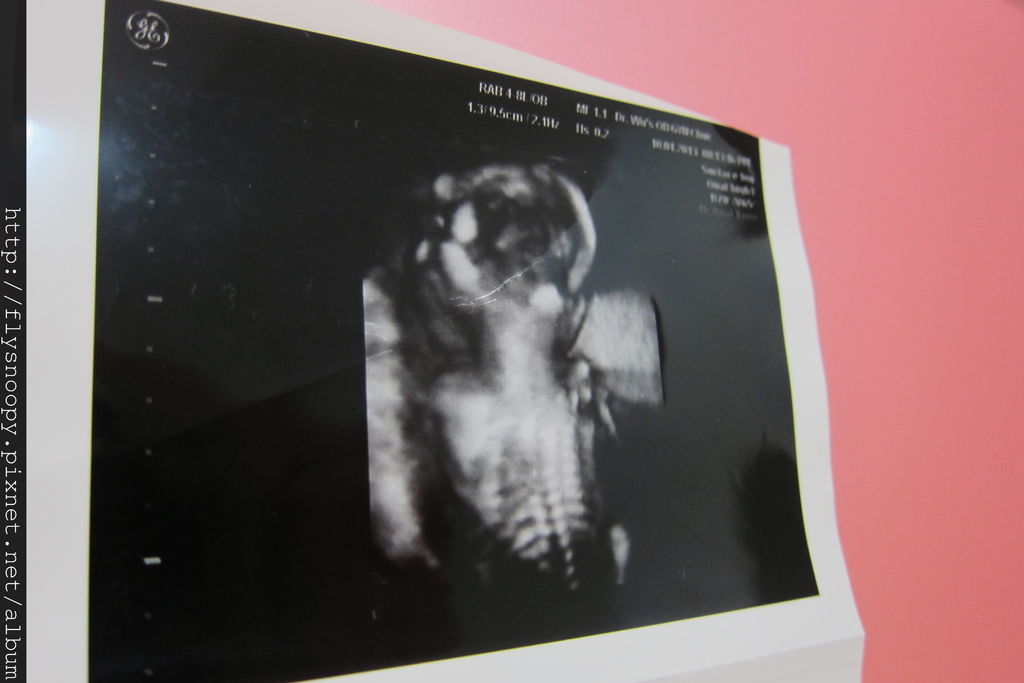

第一張照片是baby的脊椎,拍得好明顯喔,